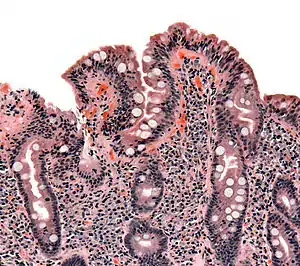

![]() Мікроскопічна картина целіакії: ворсинки тонкого кишечника сплощені, крипти гіперплазовані та інфільтровані лімфоцитами. Мікроскопічна картина целіакії: ворсинки тонкого кишечника сплощені, крипти гіперплазовані та інфільтровані лімфоцитами. | |